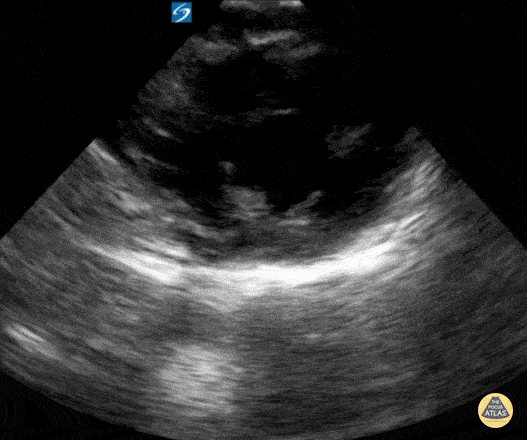

Peds-Cardiac - Older kid PSSA mid

11 year old male presented to the emergency department with chest pain. Cardiac POCUS did not reveal any abnormalities and the patient was discharged home after an EKG was performed and the chest pain improved with ibuprofen. Contributor: Zach Boivin, MD, @ZachBoivinMD